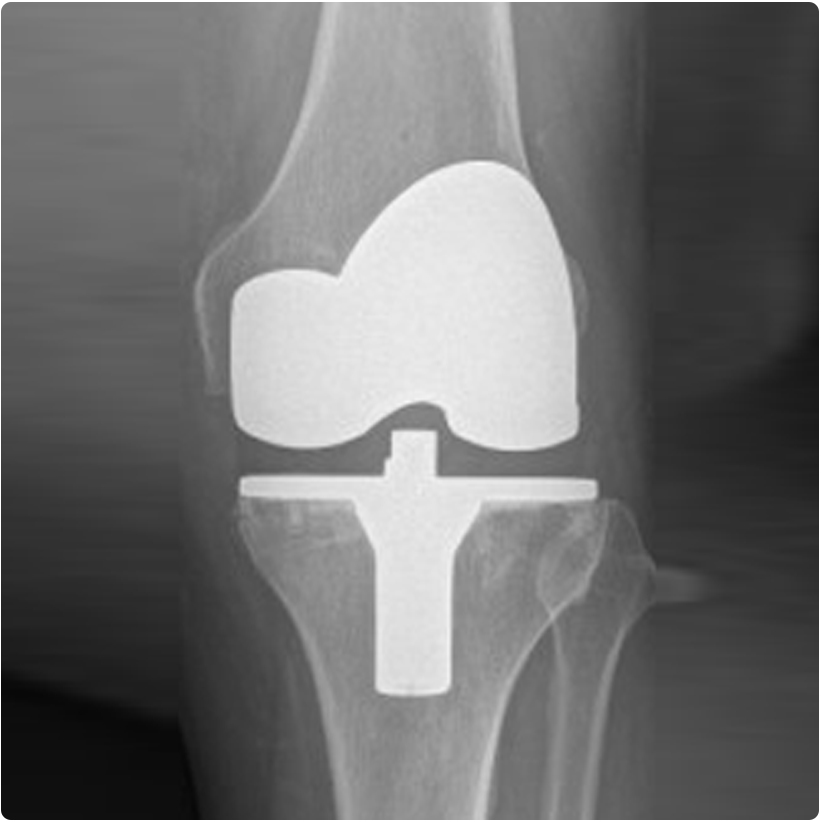

Eklemin bir bölgesinde aşınma varlığında, belli koşullar altında kısmi-parsiyel protezler yapılabilir. Daha küçük kesi ile yapılan bu protezler uygun hasta seçimiyle oldukça iyi sonuçlara sahiptir.

İlerlemiş osteoartrit varlığında ise tam total diz protezi yapılır. Günümüzde total diz protezleri sonuçları oldukça iyi düzeydedir. Diz protezleri ile ilgili bilgilere diz protezi, kısmi (parsiyel) diz protezi, kişiselleştirilmiş diz protezi ve robot yardımlı diz protezi başlıklarından ulaşabilirsiniz.